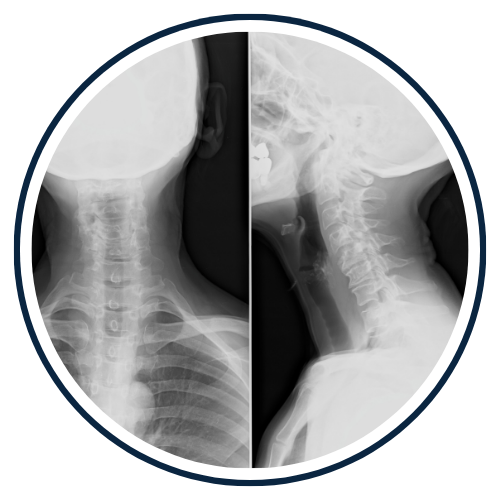

Chiropractors take x-rays to see the internal condition of the spine. X-rays also reveal if there are any underlying spinal disorders, such as arthritis of the spine, abnormal development, disc disorders, bone spurs, and spinal deterioration.

Having an x-ray taken before any adjustment helps chiropractors make a correct diagnosis. Combining x-rays with other exams will benefit the patient ultimately.